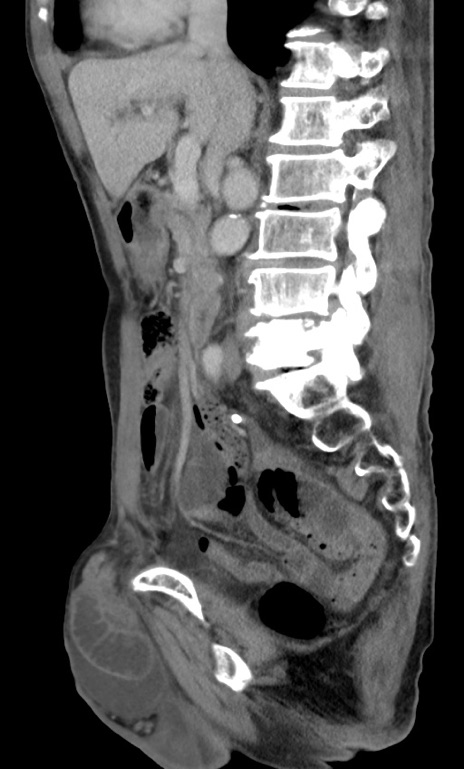

症例3(矢状断像)

【症例】 70歳代男性

【主訴】右鼠径部腫瘤、疼痛

【現病歴】本日朝より上記主訴あり、受診。

【既往歴】膀胱癌にて膀胱全摘、両側尿管皮膚瘻

【データ】WBC 5600、CRP 0.56